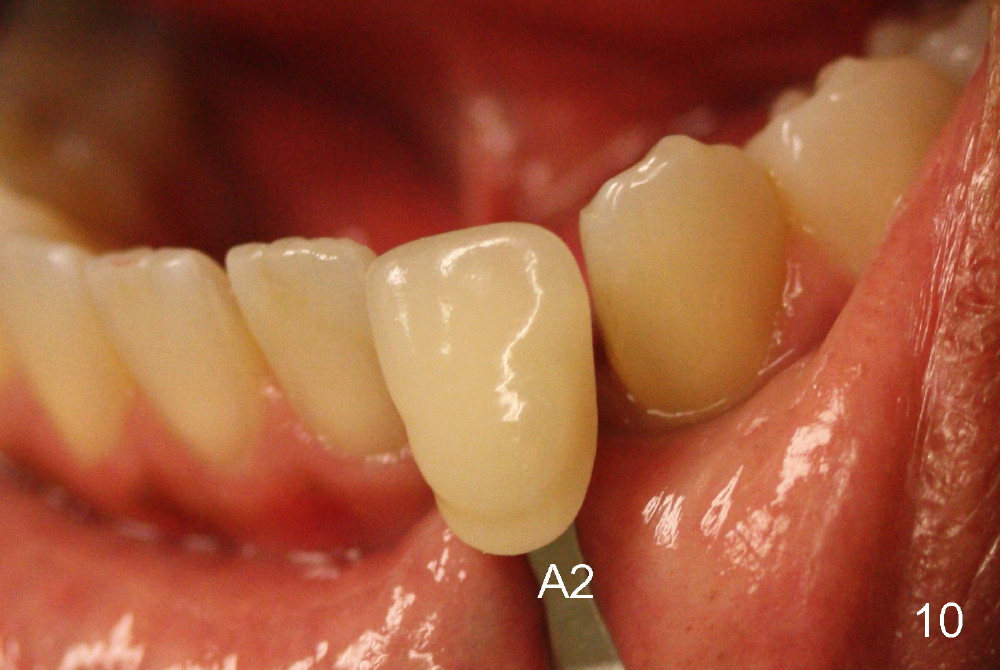

Fig.10: A2 shade guide. The patient requests A1 for the incisal edge and body and A2.5 for the cervical region. Fig.11 is taken 22 months post 2nd cementation (4 years postop). The implant crown remains normal 1 year 10 months post 2nd cementation (4 years 10 months postop, Fig.12,13).